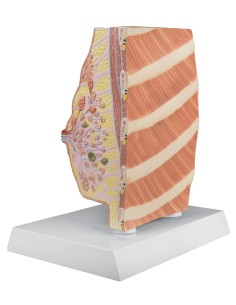

Modèle de palpation mammaire, trois seins simples sur support - 3B Scientific L55

Modèle de palpation mammaire, trois seins simples sur support - 3B Scientific L55

Modèle de palpation mammaire, à suspendre - 3B Scientific L51

Modèle de palpation mammaire, à suspendre - 3B Scientific L50